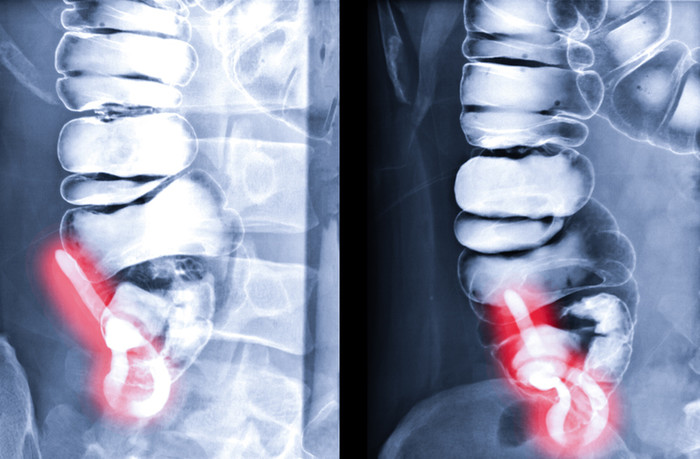

맹장이란 보통 배 오른쪽 아래에 있다. 그렇지만 성별이 달라지면 맹장이 있는 곳이 다르다는 의견도 있다. 이는 맹장염 환자마다 통증이 느껴지는 부위가 다를 수 있어서다. 하지만 맹장이 있는 곳은 차이가 없는 관계로 사람마다 맹장의 위치가 같은 곳에 있는 것이다. 다만 여성은 임신을 했을 때 배가 나오게 되면서 배 위 오른쪽으로 맹장이 올려지기도 한다. 그러므로 우측 상단의 배가 아파도 병원에 가봐야 한다. 한편 태어났을때부터 원래 왼쪽에 맹장이 있을 수 있다. 하지만 맹장에 염증이 생기면 통증이 심한 관계로, 아픔 때문에라도 병원을 찾아가는 것은 같다.